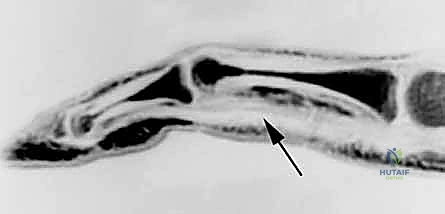

الخطوة 4: إدخال قضيب السيليكون (Hunter Rod Insertion)

الآن، أصبح المسار خالياً. يقوم الجراح بقياس حجم النفق المتاح، ويختار قضيباً من السيليكون الطبي المرن (يُعرف باسم Hunter Rod). يتم تمرير هذا القضيب عبر النفق (من أسفل البكرات A2 و A4) وصولاً إلى طرف الإصبع.

الخطوة 5: التثبيت والإغلاق

يتم تثبيت الطرف البعيد (Distal end) من قضيب السيليكون بقوة في بقايا الوتر العميق عند السلامية البعيدة، بينما يُترك الطرف القريب (Proximal end) حراً ومسترخياً في منطقة راحة اليد أو الساعد (المنطقة 3 أو 5). يتم إغلاق الجروح بعناية فائقة.

هنا تتجلى قدرة الجسم على التكيف. يتعرف الجسم على قضيب السيليكون كجسم غريب، ولكنه بدلاً من رفضه (لأنه خامل بيولوجياً)، يقوم بتكوين غلاف نسيجي رقيق وناعم جداً حوله. هذا الغلاف يُسمى "الغمد الكاذب" (Pseudosheath).

خلايا هذا الغمد الجديد تفرز سائلاً زليلياً مشابهاً للسائل الطبيعي للمفاصل. وبفضل العلاج الطبيعي السلبي (Passive motion) الذي يقوم به المريض خلال هذه الأشهر، ينزلق قضيب السيليكون داخل إصبعه، مما يجعل الغمد الجديد أملساً وخالياً تماماً من الاحتكاك أو الالتصاقات. لقد تم تجهيز التربة الخصبة لزراعة الوتر الحقيقي!